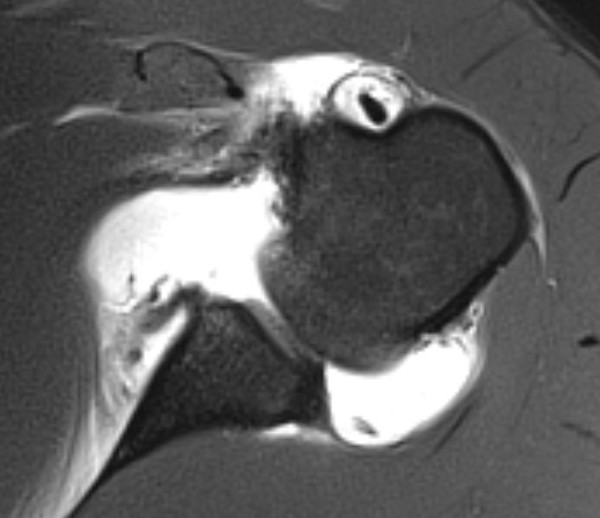

Anterior labral tears

Bony bankart / anterior glenoid deficiency